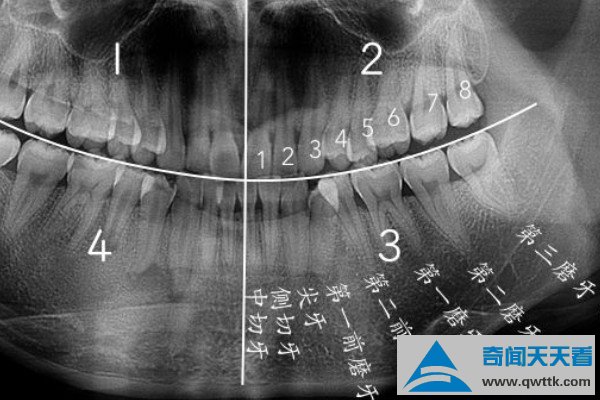

智齿是人类口腔内牙槽骨上最里面的第三颗磨牙,由于它经常会产生疼痛感,很多人选择将其拔掉,但部分人表示拔智齿后悔死了,那么这是为什么呢?快和小编去看看吧。

人在成年之后一般都会长智齿,在其生长期间可能会出现牙龈肿痛的情况,严重影响人们的日常生活,所以很多医生都建议将其拔掉,但总有人会因为拔掉后出现的不良反应而后悔。事实上,智齿对人的危害没有那么大,如果其生长状态比较良好,则没有强行拔除的必要,除非是畸形智齿。